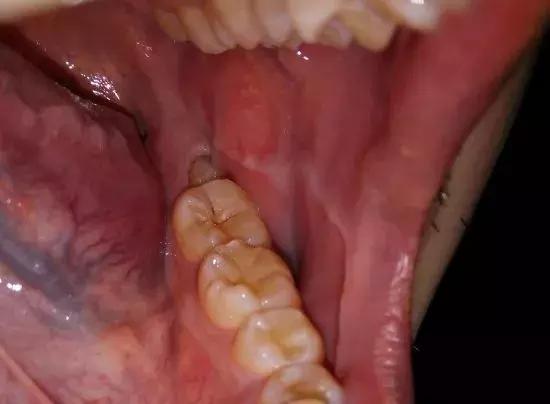

智齿斜靠在第二磨牙上,导致邻牙龋坏

不要高估你的动手能力,也不要挑战自己的耐性,刷不到,真的刷不到,放弃吧。

买了尽头刷就能做到每天清理歪头的智齿了吗,这就是大多数人嘴里智齿的清洁程度↓